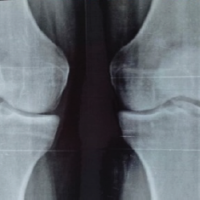

A 23-year-old male with no known comorbidities presented with complaints of pain, swelling, and instability over the right knee following twisting injury while playing football 3 years back. On examination of the knee, there was no healed scar suggestive of any external injury. There was minimal swelling of the right knee and varicose veins all over the right lower limb. The right lower limb was found to be 1 cm longer than the left, accounted by 0.5 cm in the femur and 0.5 cm in tibia. The bulk of the thigh and leg was larger by 1.5 cm on the right side compared to the left side (Fig. 1 is self-explanatory). There was a port-wine stain over the lateral aspect of the right thigh (Fig. 2). He did not have any features suggestive of ligamentous laxity. The knee range of movement was full. Posterior sag sign was present. The posterior drawer test was positive. Varus and Valgus stress tests were negative. The McMurray test for both menisci was negative. Dial test and pivot shift test were negative. Tests for ACL insufficiency were negative. X-ray standing anterior–posterior (Fig. 3), 45° flexion, weight bearing, and merchant patellar views were taken with contralateral view for comparison. This showed a positive sag compared to the contralateral knee.